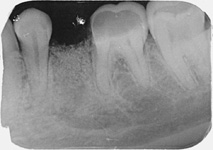

Při ztrátě molárů a premolárů v horní čelisti a jejich náhradě implantáty se často setkáváme s nedostatečnou vertikální nabídkou kosti pod čelistní dutinou, často doprovázenou i nedostatečnou horizontální nabídkou a sníženou kvalitou kosti

(v oblasti 2. premoláru v 50%, v oblasti moláru až v 80% případů nedostatečná kostní nabídka)

Jedná se o vyzvednutí membrány, která čelistní dutinu vystýlá, pod vyzvednutou membránou vznikne kapsa, kam se umístí augmentační materiál, do kterého se zavedou implantáty.